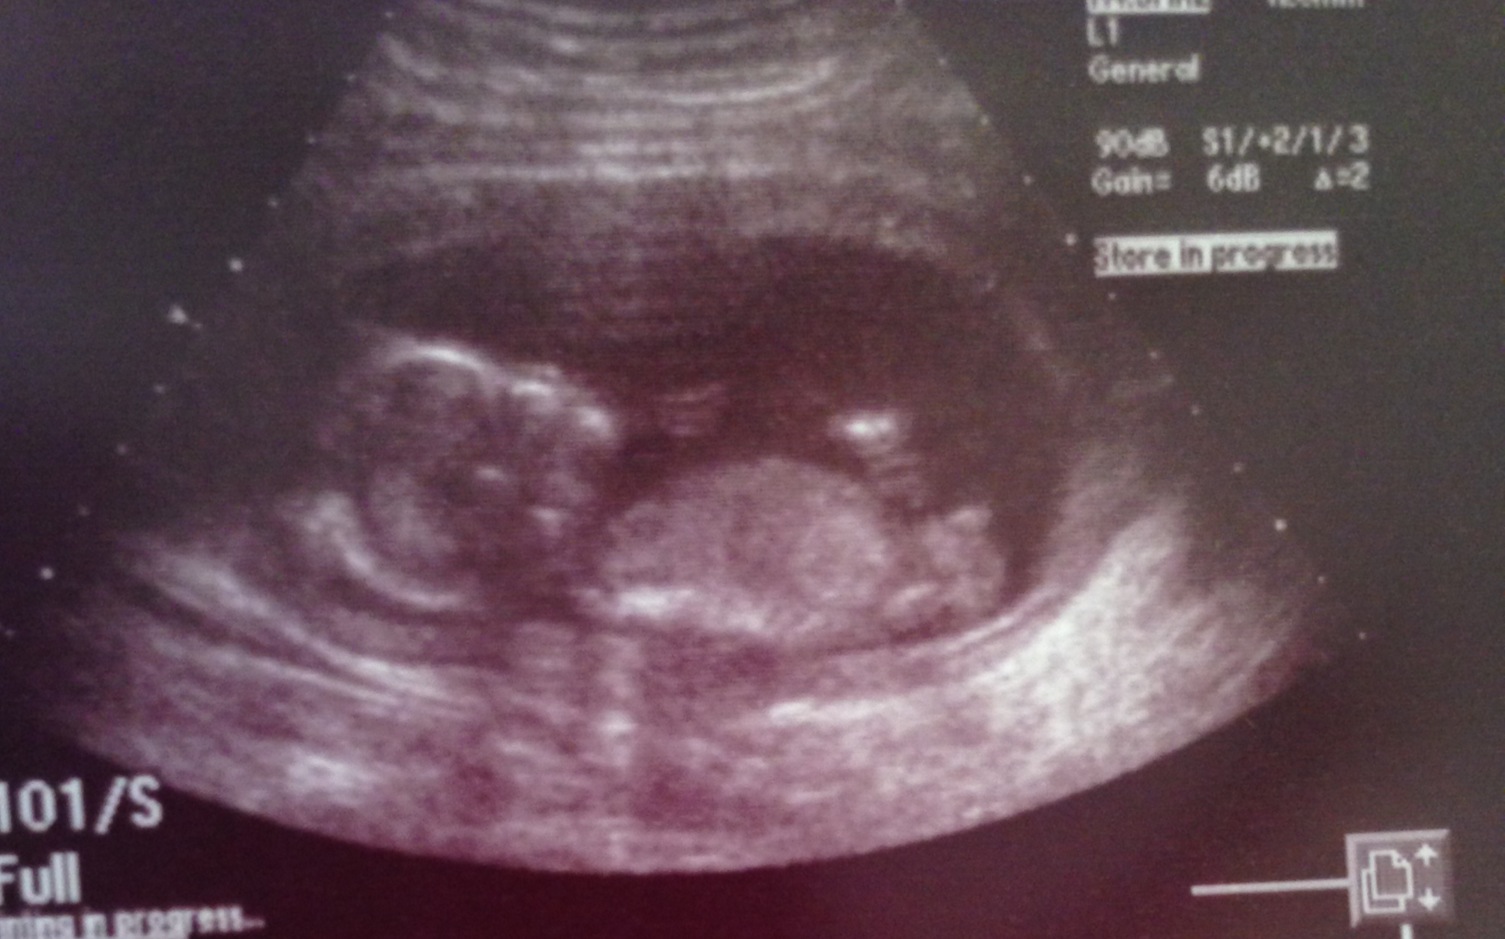

This is a later shot at 20 weeks but see how it looks snail-ish? I'll keep looking for a 15 week example but it would be similar or appear "stacked" as 2 bumps.

Attachment 10741

Ok I think I see what you are saying. I added a second image to show you what I believe you are explaining. As you can tell this is my first pregnancy :happy: and i'm probably asking stupid questions! Again thank you for helping me. If you do come across a 15 week profile please let me know.

Yes, that is the scrotum and the other arrow that was already on the image is pointing to the penis.

Ok thank you so much I finally see it!! So at 15 weeks would the penis be vertical or is it still valid to measure it against the spine?

At 15 weeks you wouldn't measure the angle of a boy anymore--it just wouldn't be necessary as it is VERY different from a side shot of a girl. Only inexperienced guessers would get them confused. Hope that helps :)